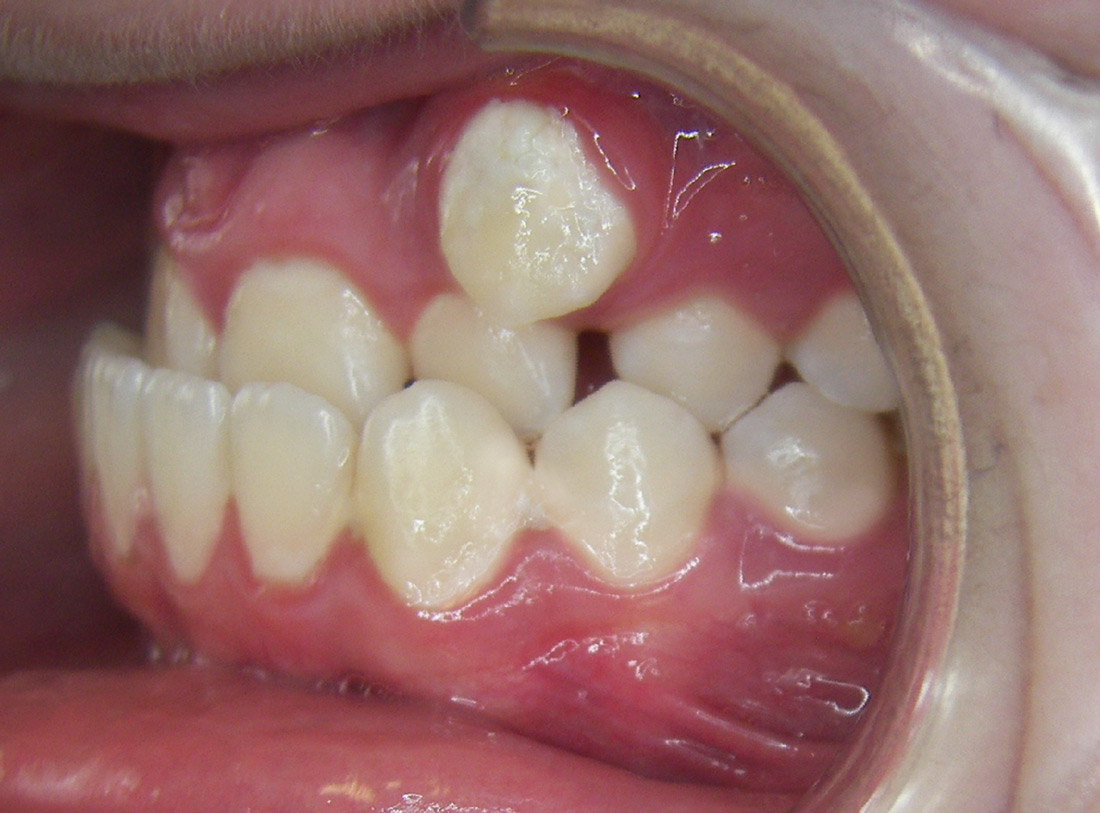

Case Studies

We’re proud of our patients’ new smiles, and most times, they’re even more proud to show them off. You’ll be ready for your close-up, too, once you visit the friendly experts at LB Orthodontics. Click here to see our smile gallery.